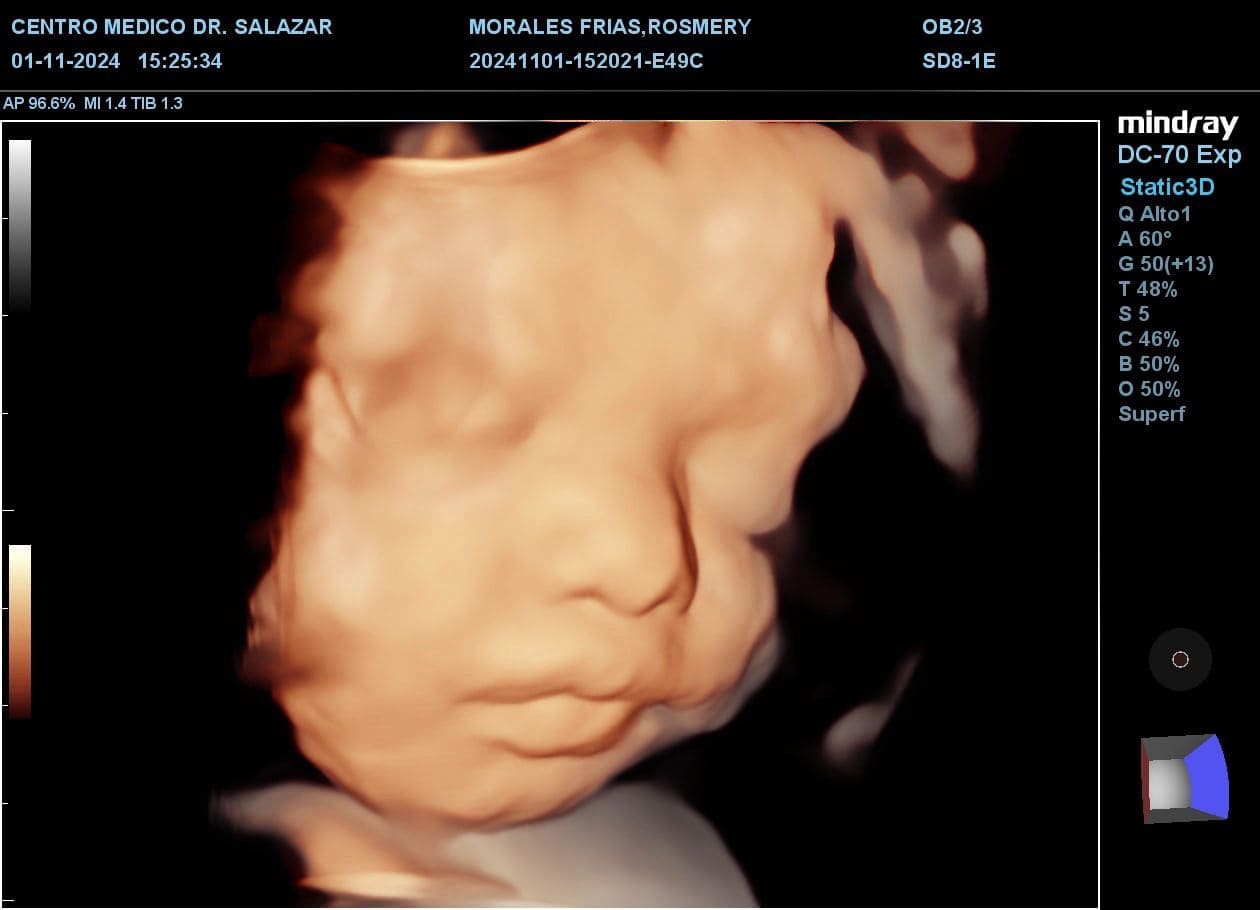

ECOGRAFÍA MORFOLOGICA

Se realiza entre las 20 a 24 semanas de gestación. En esta ecografía, además de tomar las medidas de tu bebé, se realiza un examen detallado de toda su morfología, órgano por órgano, que da la posibilidad de diagnosticar anomalías en su desarrollo; por lo tanto, en esta ecografía se pueden diagnosticar gran parte de malformaciones que pueda presentar.